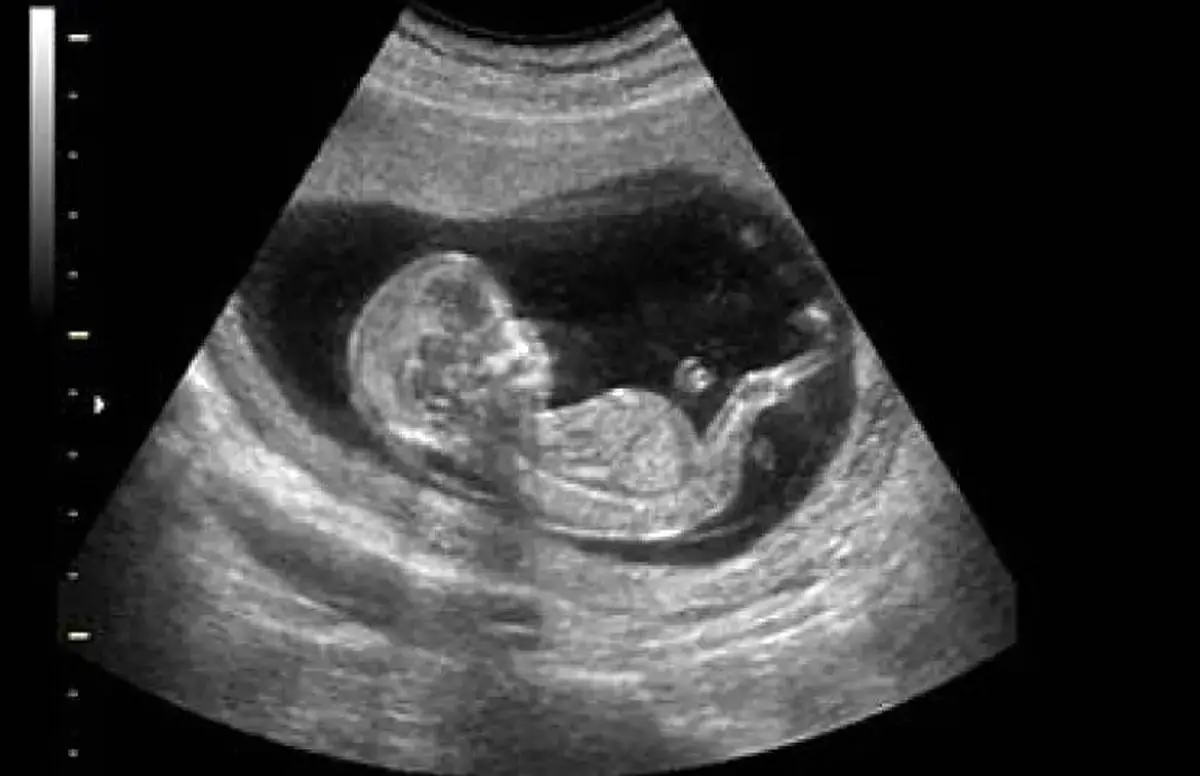

مدیر گروه ایمنی‌شناسی تولید مثل پژوهشگاه ابن‌سینا گفت: حدود سه میلیون زوج نابارور در کشور وجود دارد و سالانه ۵ درصد به این آمار افزوده می‌شود و متاسفانه این موضوع به تهدیدی برای امنیت جمعیتی ایران تبدیل شده است.

مدیر گروه ایمنی‌شناسی تولید مثل پژوهشگاه ابن‌سینا تأکید کرد: ناباروری تنها یک مسئله پزشکی نیست، بلکه چالشی اجتماعی است. مطالعه‌ای که حدود ۱۲ تا ۱۳ سال پیش در پژوهشگاه ابن‌سینا روی ۱۹ هزار زوج از سراسر کشور انجام شد نشان داد که حدود ۱۹.۷ درصد زوج‌های ایرانی نابارور هستند؛ به عبارتی از هر ۶ زوج، یک زوج با مشکل ناباروری مواجه‌اند.

مدیر گروه ایمنی‌شناسی تولیدمثل پژوهشگاه ابن‌سینا با استناد به داده‌های ملی اظهار کرد: در حال حاضر حدود سه میلیون زوج نابارور در ایران وجود دارد. طبق مطالعات، از هر شش زوج ایرانی، یک زوج با ناباروری مواجه است و سالانه حدود پنج درصد به این آمار افزوده می‌شود.